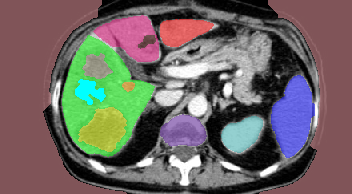

Abdominal Organ Segmentation:

We used CT dataset and extended the work in [13] which used Hedgehogs to segment liver and kidneys. In contrast to [13], we utilized more detailed structures reaching labels.

For each test case we computed the weighted precision

where is the ground truth labeling. The weighted recall is defined similarly. As shown in Table 3, all methods performed comparably due to the use of Hedgehog priors and the star-like structure of , which -exp is well suited for. See Table 4 for results without using Hedgehog priors. Figure 18 shows the tree and our result for one test case. Interestingly, QPBO labeled all the pixels in all 7 test cases. By comparing Tables 3 and 4 it is easy to see the benefit of using Hedgehog priors. Moreover, Path-Moves outperformed QPBO and a-exp after dropping the Hedgehog priors.